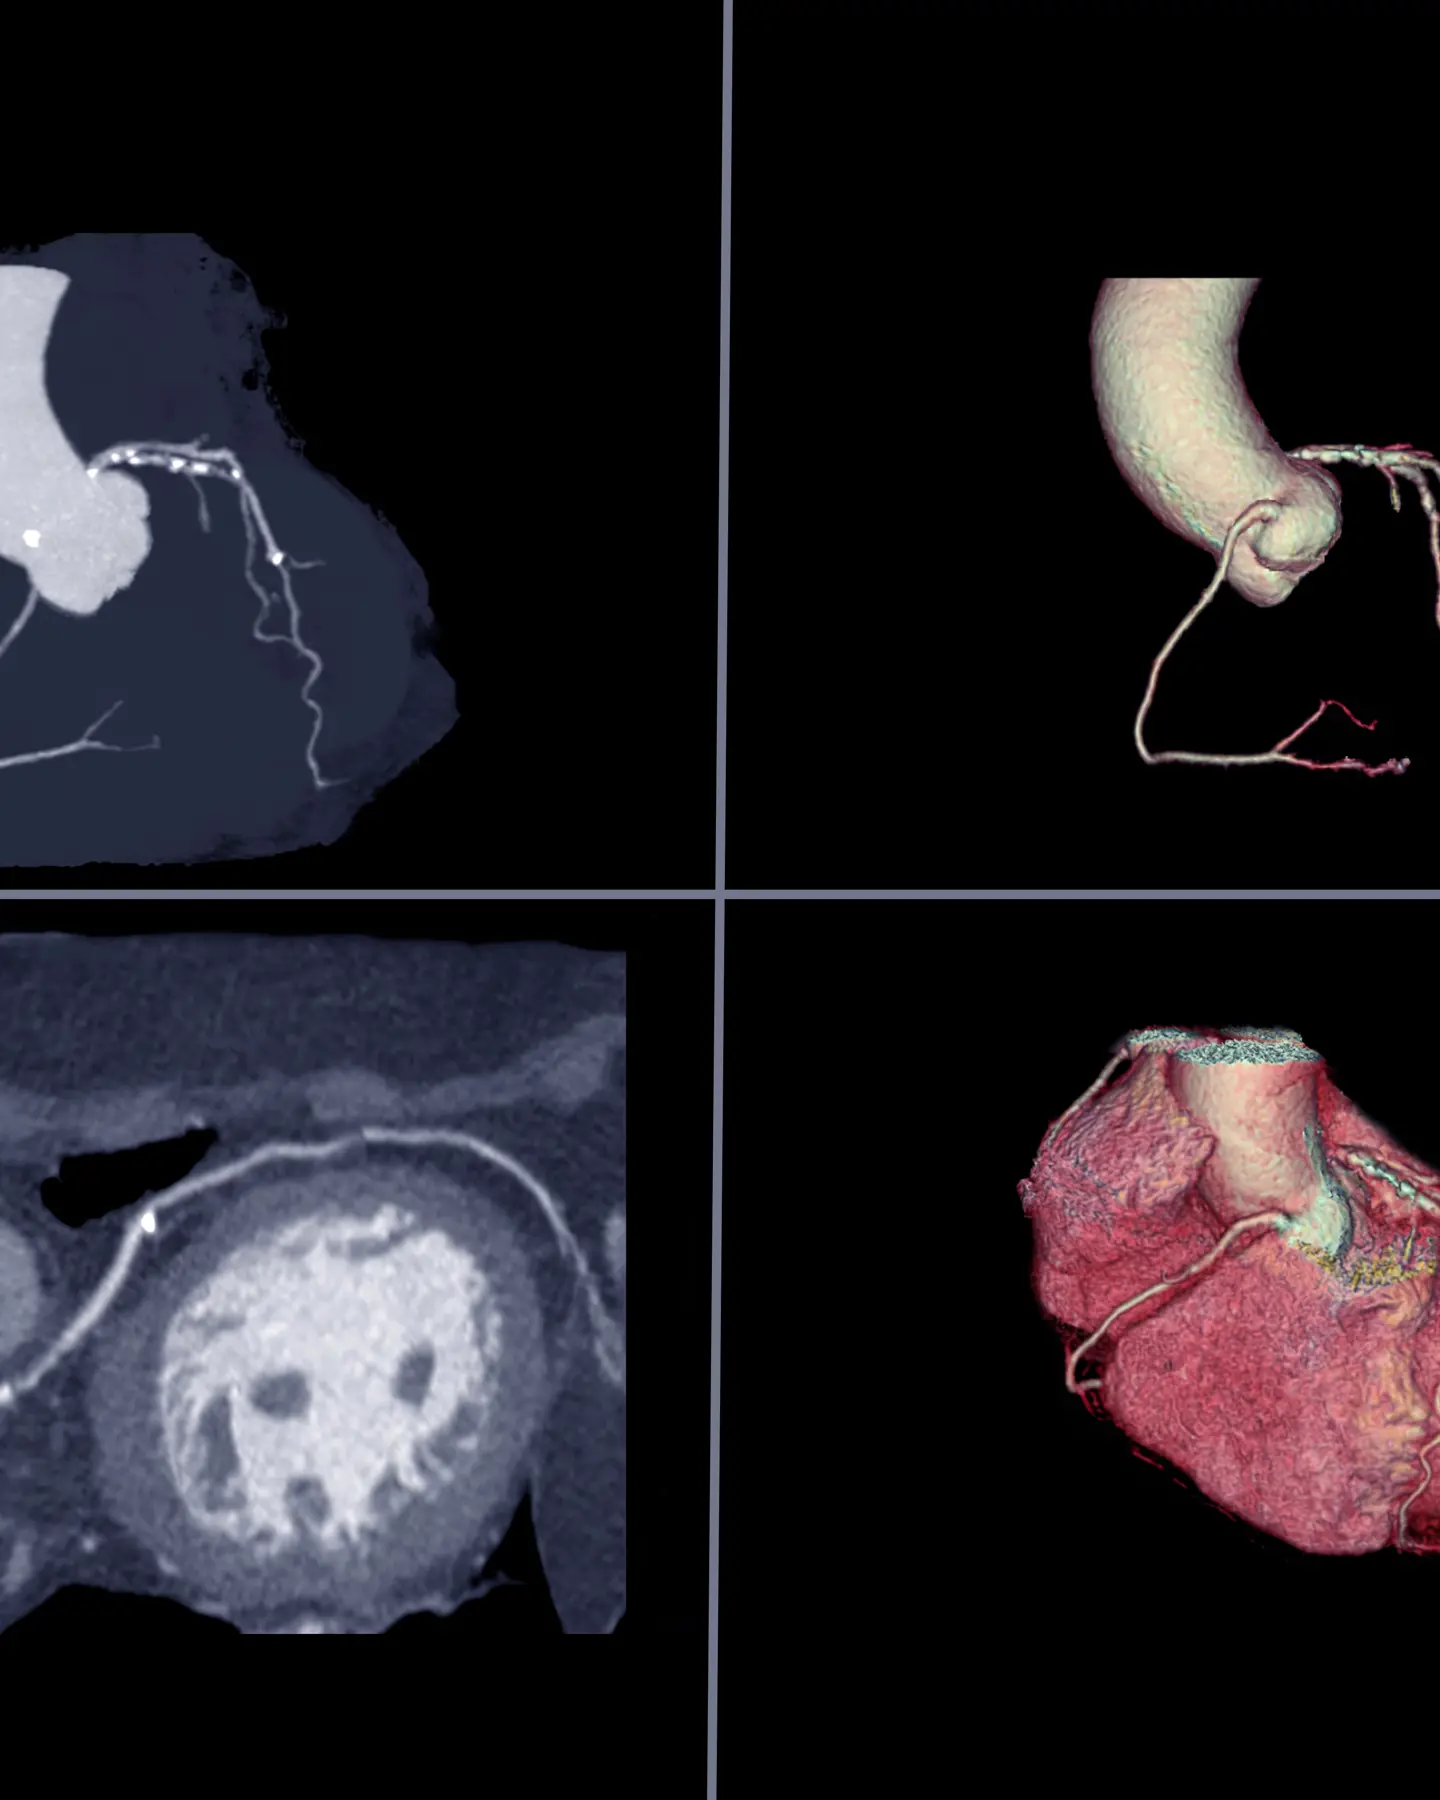

Cardiac CT is a non-invasive test that uses X-rays. It creates detailed images of the heart and blood vessels. This test can find issues such as blocked arteries, calcium buildup, or structural heart problems. Doctors often use it to check heart disease risk or to explore symptoms like chest pain.

CT coronary angiogram

If appropriate, your Vista Health GP may recommend a CT coronary angiogram. This is a non-invasive scan that uses advanced X-ray technology to produce detailed images of your heart and coronary arteries. It helps identify any narrowing or blockages of your coronary blood vessels and assess your risk of heart disease or heart attack. This, therefore, helps guide the best next steps for your care.

Calcium scanning

A CT calcium scan is a quick, non-invasive test that uses X-rays to measure calcium build-up in your coronary arteries. The presence of calcium indicates hardened plaque, which can reduce blood flow to your heart. By detecting these early signs of coronary artery disease—often before symptoms appear - the scan gives a reliable picture of your risk of heart attack. This, therefore, helps guide preventative steps to protect your heart health.